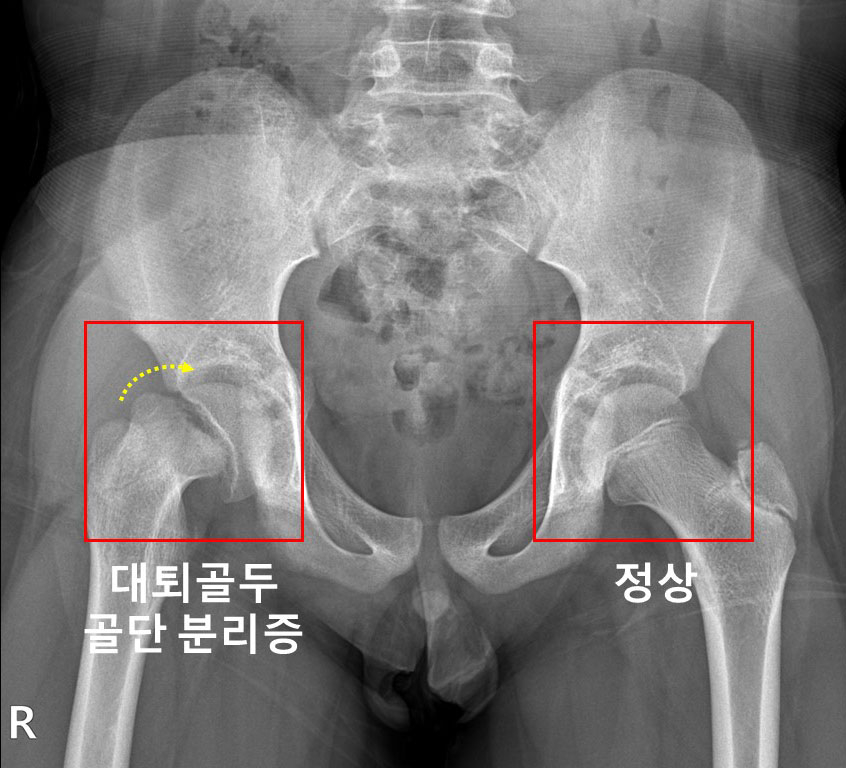

허벅지뼈(대퇴골)의 윗부분을 대퇴골두라 한다. 외상을 입지 않았는데도 대퇴골두가 분리되는 질환이 '대퇴골두 골단 분리증'이다. 주요 원인으로 내분비질환이 꼽히는데, 내분비질환을 앓는 소아청소년 환자에서의 대퇴골두 골단 분리증의 발병률을 한국 연구진이 세계 최초로 규명했다.

허벅지뼈(대퇴골) 위쪽의 성장판 부위에서 대퇴골두와 그 아래 뼈가 특별한 외상이 없는 데도 분리될 때 대퇴골두 골단 분리증으로 진단한다. 진단이 늦어지면 대퇴비구 충돌증후군, 대퇴골두가 썩는 대퇴골두 무혈성 괴사가 발생할 수 있다.